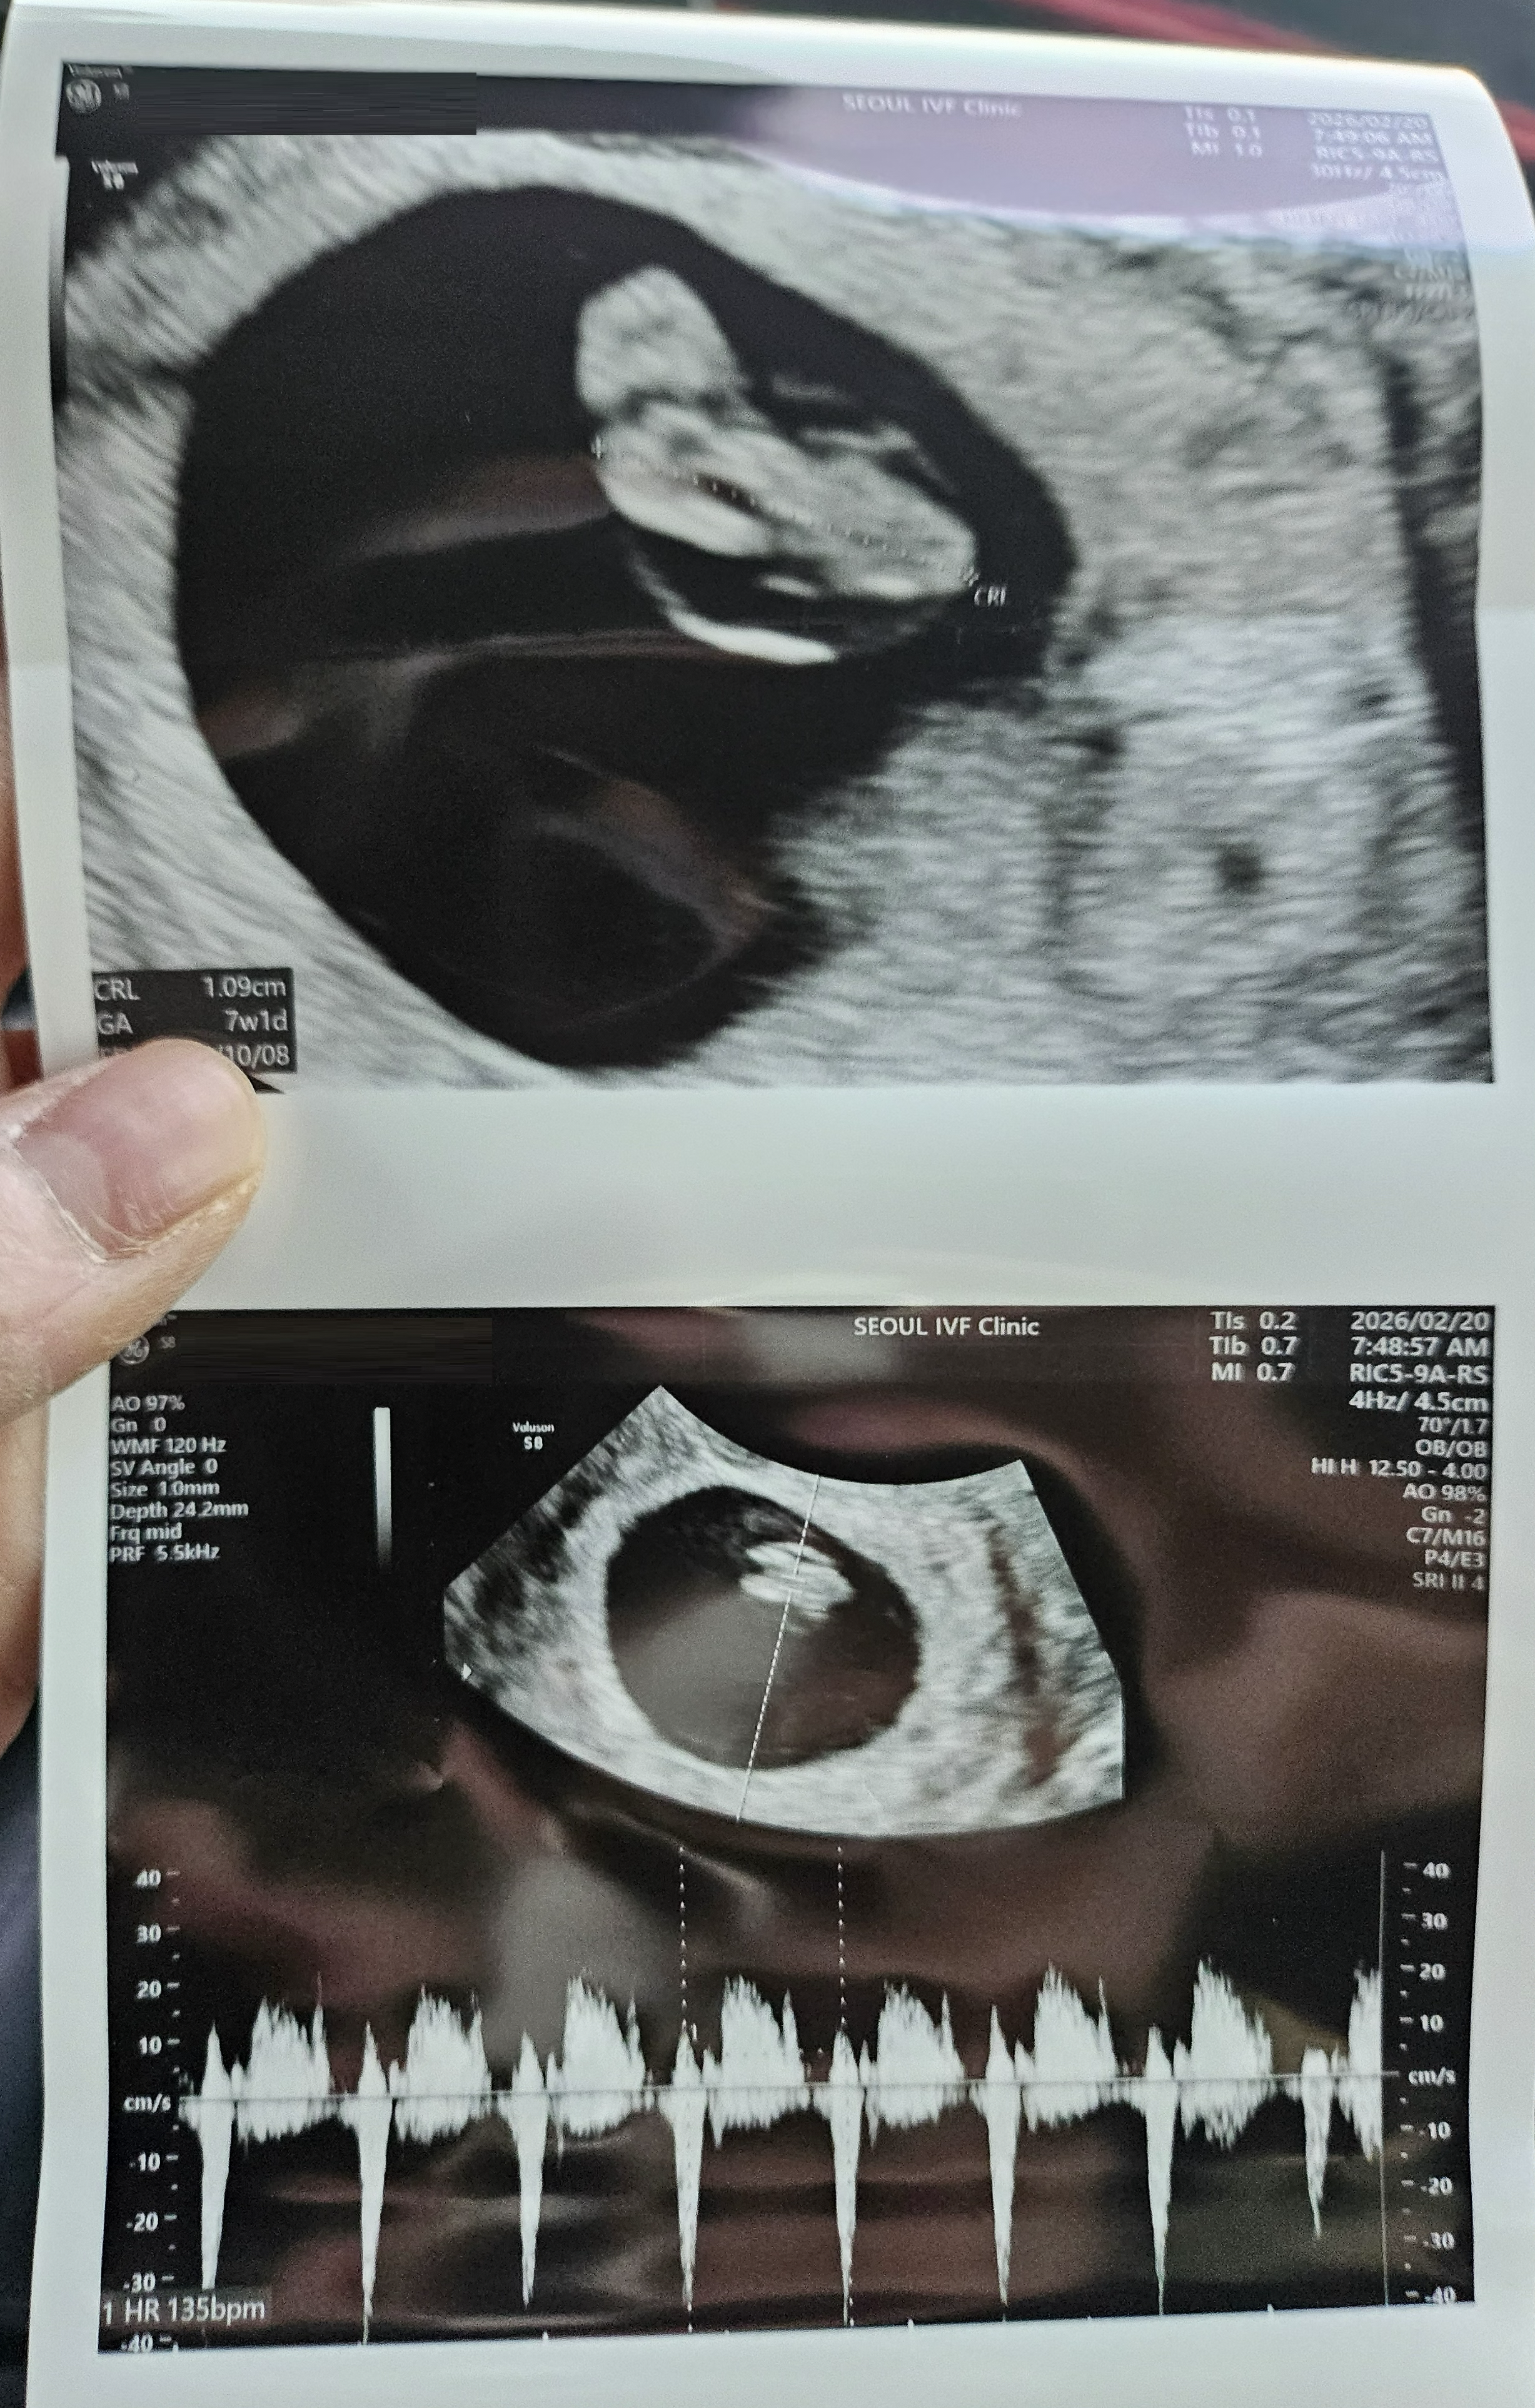

| 가슴 떨리는 임신 이야기를 공유해 주세요. | 처음 임신을 결심하고 6개월 동안 자연임신을 시도했지만 매달 실패를 경험했고, 타 병원에서 인공수정 2회를 진행했지만 결과가 좋지 않았습니다. 직장을 다니며 병원을 다니는 것도 쉽지 않아 고민하던 중, 종달새진료를 진행하며 맘카페를 통해 인천에서 유명하다는 정보를 접하고 서울아이비에프여성의원으로 옮기게 되었습니다. 첫 상담에서 간호사 선생님들과 이경훈 원장께서 너무 친절하게 대해주셔서 마음이 편안해졌고, “여기서 하면 임신이 될 것 같다”는 느낌이 강하게 들어 시험관 시술을 결정하게 되었습니다. 첫 채취에서 5개의 난자를 얻었고, 그 5개가 모두 수정되는 좋은 결과를 얻었습니다. 이후 첫 번째 동결이식에서 임신에 성공해 현재 아기를 품고 있으며, “나도 임신이 될 수 있는 몸이었구나”라는 생각에 행복한 시간을 보내고 있습니다. |